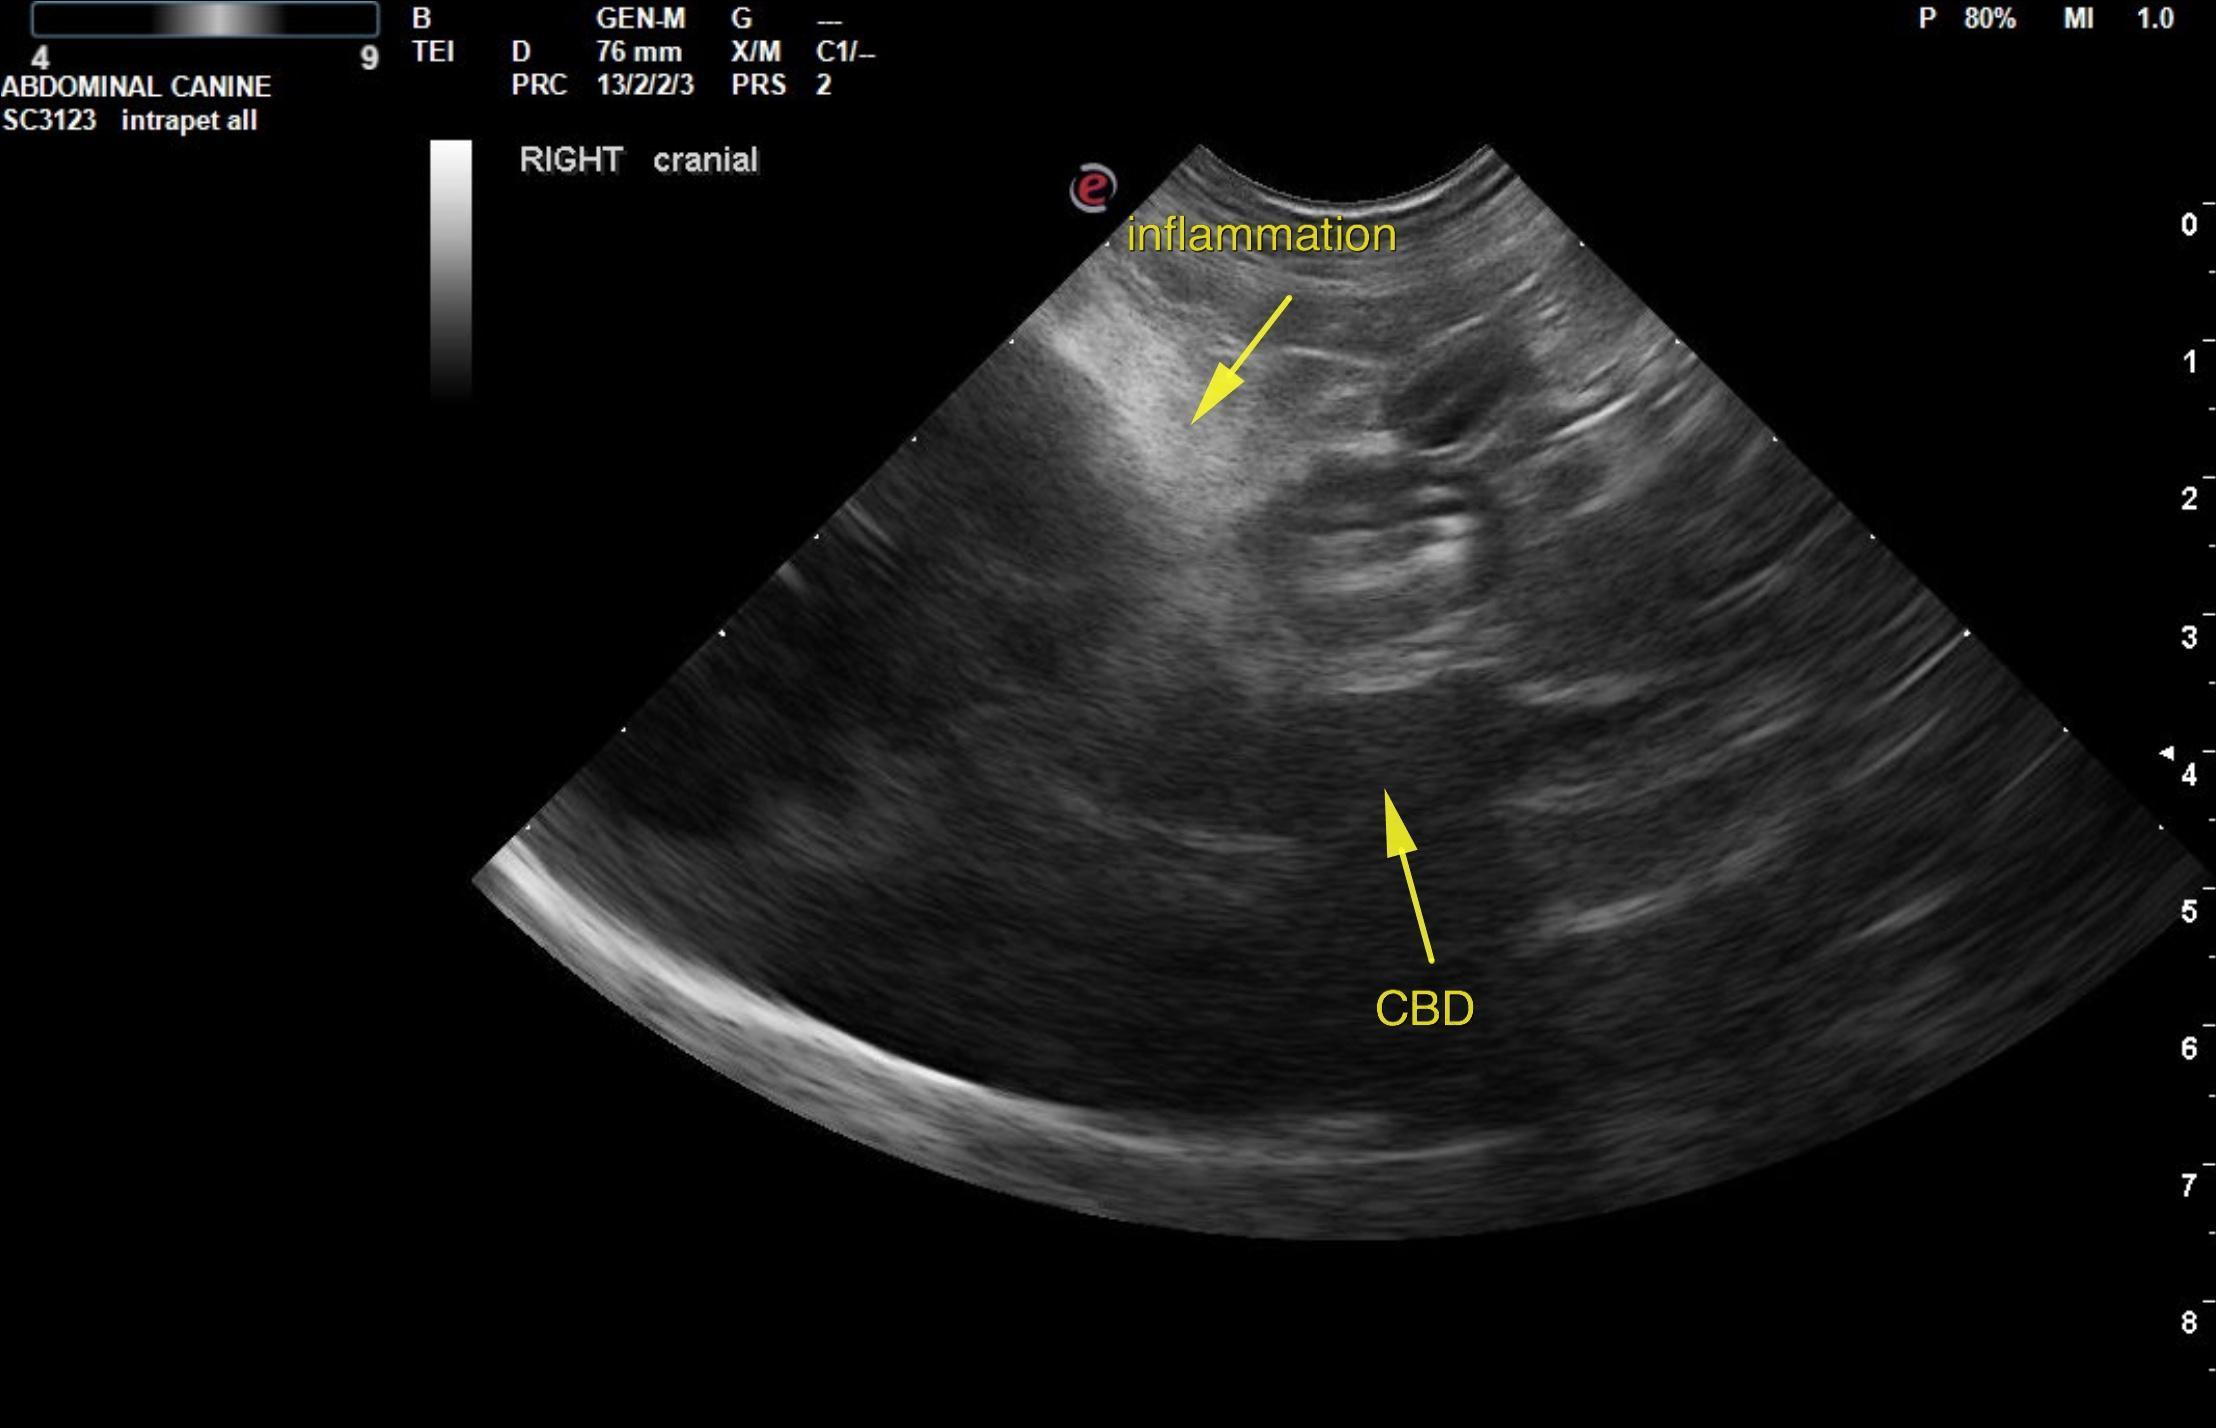

This 10 year old M ShihTzu dog started vomiting 4 days ago and has progressed in frequency. Lethargic.

Chem: ALKP 367, ALT>1000, GGT 24, elevated LE